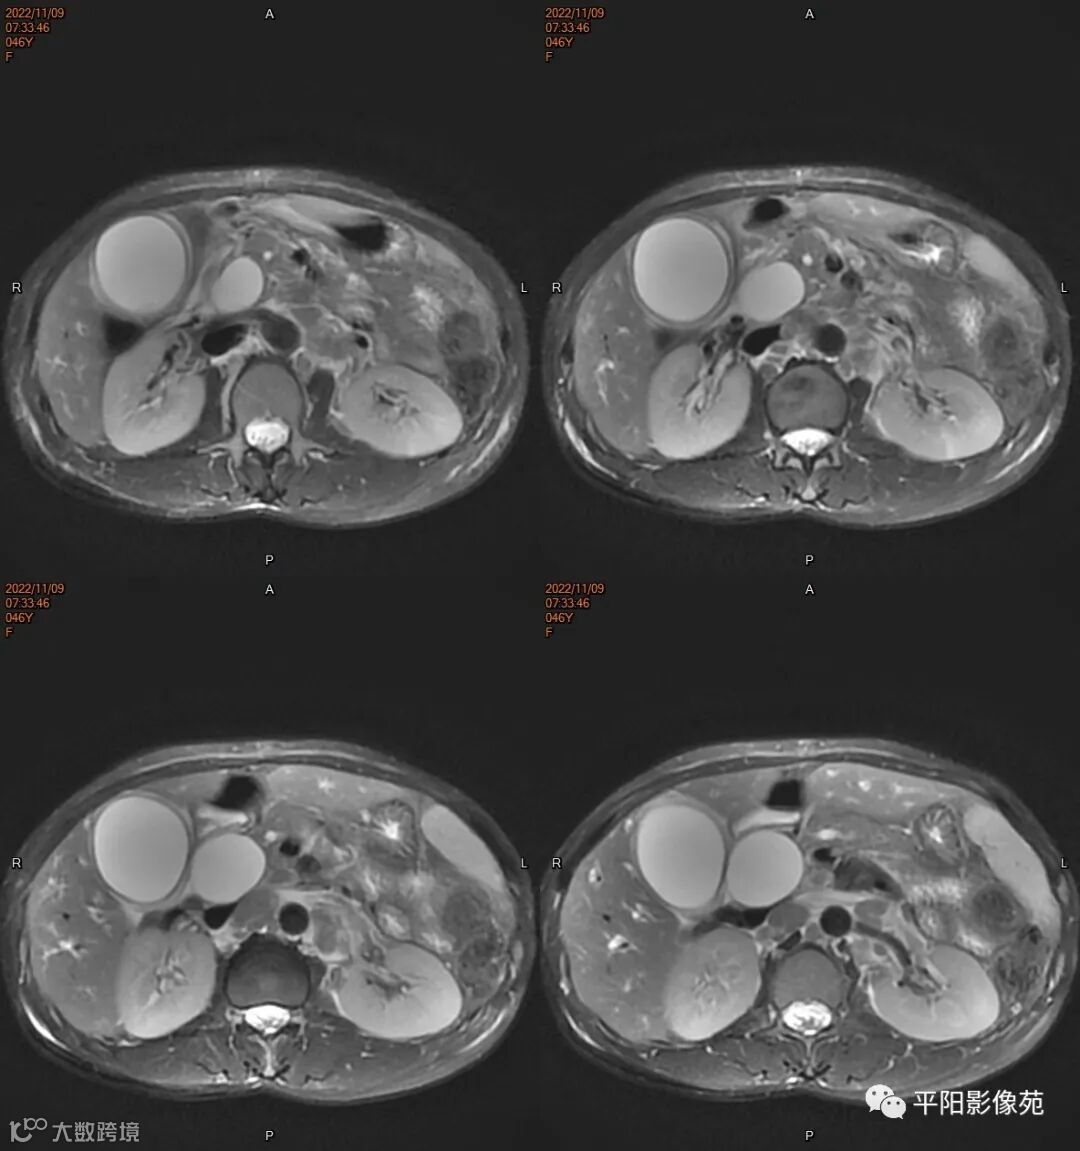

MR

影像表现: